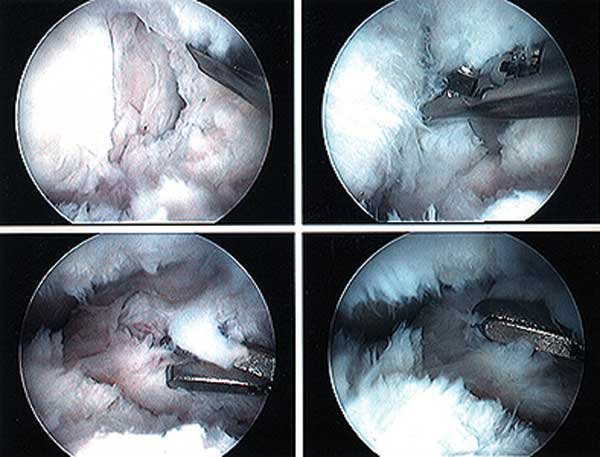

At this point, arthroscopic debridement and removal of scar tissue throughout the knee joint can be effective in solving a limitation of knee extension, flexion, or both. The figure shows a knee that has extensive scar tissue deep inside the joint.

A demonstration of an arthroscopic technique for debridement of contracted tissues in a knee with arthrofibrosis is shown in the figures below.

This patient had a restriction in medial-to-lateral translation (glide) of the patella, with a contracture of the medial and lateral retinaculum. However, there was still 50% of normal patellar mobility present indicating that an arthroscopic technique could be used and an open extensive technique was not necessary. There was a limitation of motion of 0/5/90°.